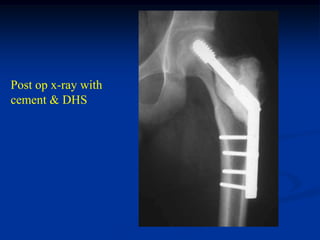

20 year male with chondroblastoma & ABC prox femur

tumor

Axial T-2 MRI

Coronal T-2 MRI

edema

Photomic

Post op x-ray with

cement & DHS